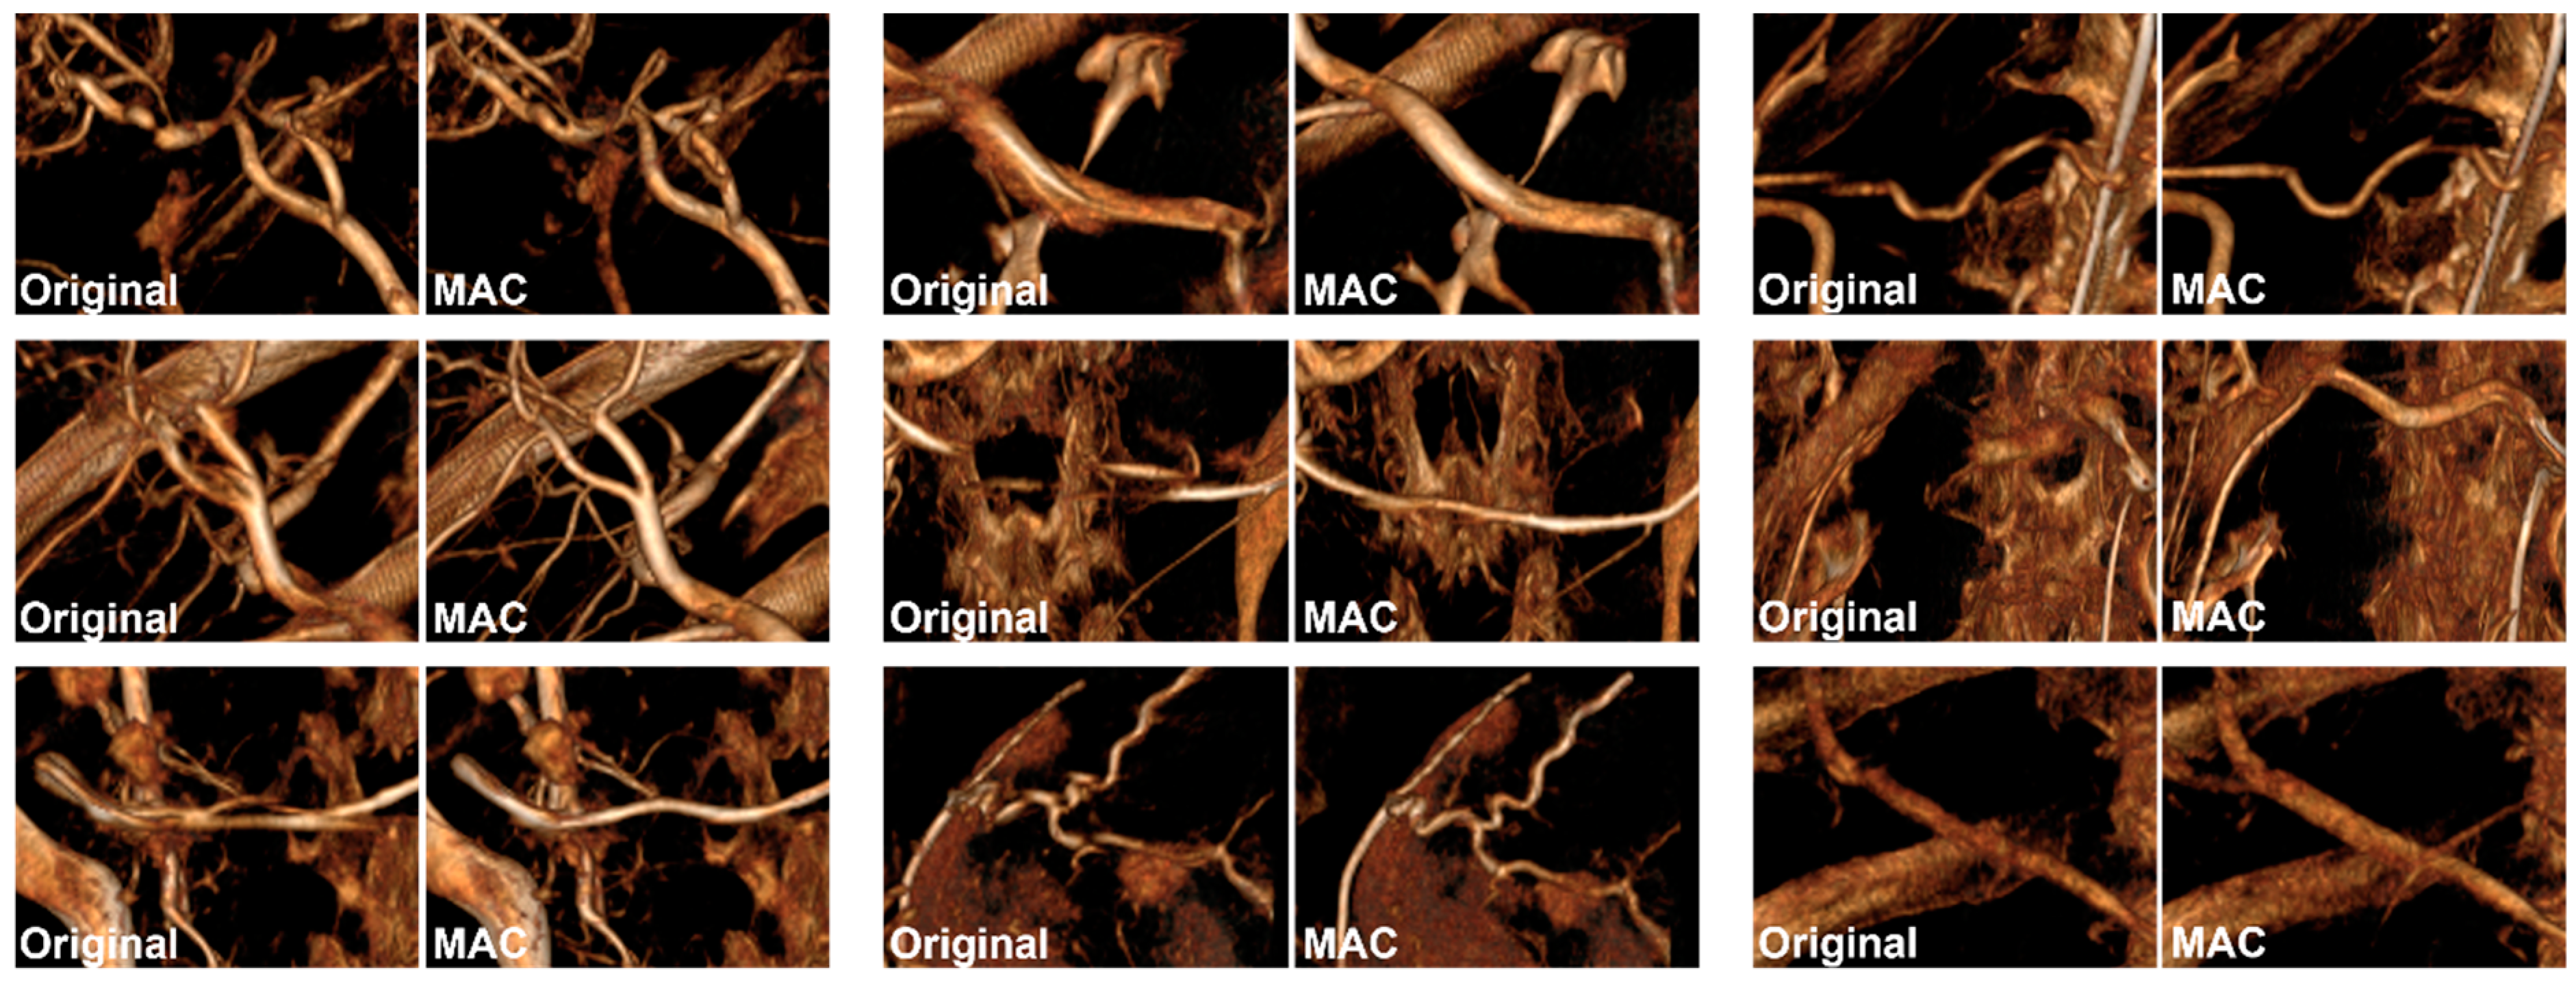

2. Materials and Methods

2.4. Experiment 2